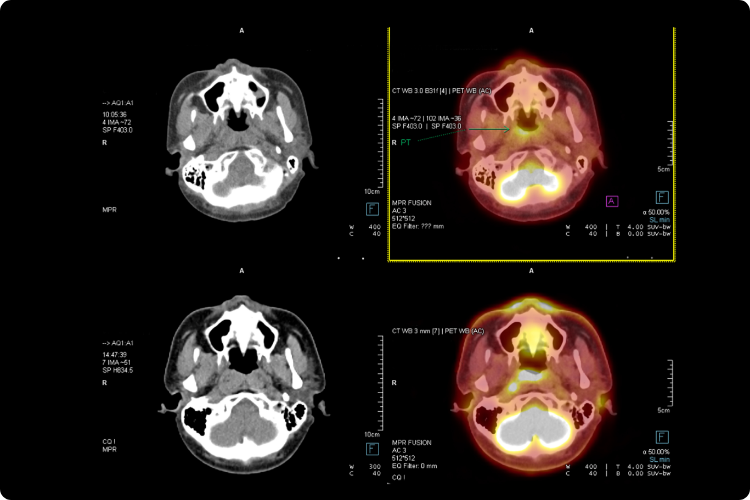

Detectar el cáncer en etapas tempranas aumenta significativamente la supervivencia.

- La detección temprana salva vidas.

El cáncer detectado a tiempo tiene mayores posibilidades de tratamiento exitoso.